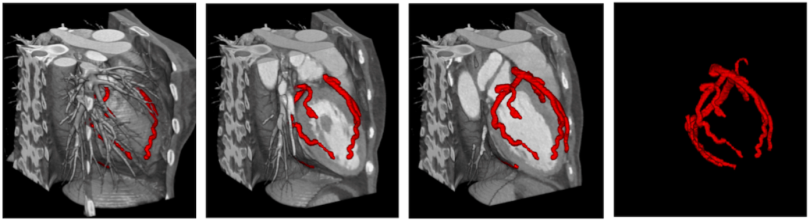

在心臟電腦斷層影像中,除了不需顯影劑的鈣化分析影像,還有需注射顯影劑的電腦斷層血管攝影。急性心肌梗塞的發生也與非鈣化性斑塊的破裂或腐蝕(erosion)有關,因此需要對比劑強化心臟電腦斷層血管影像(CCTA),其藉由增強冠狀動脈血液的訊號,才能夠辨識非鈣化的斑塊,並更進一步確認血管的狹窄程度。藉由深度學習的模型,能夠開發出自動辨識CCTA影像,並偵測出冠狀動脈結構與定位斑塊病灶,能夠協助臨床診斷醫師更有效率地完成判讀,並輔助產生報告,加速診斷流程,減少病患等待影像報告時間。

圖二、萬芳團隊使用有效率軟體標記血管位置